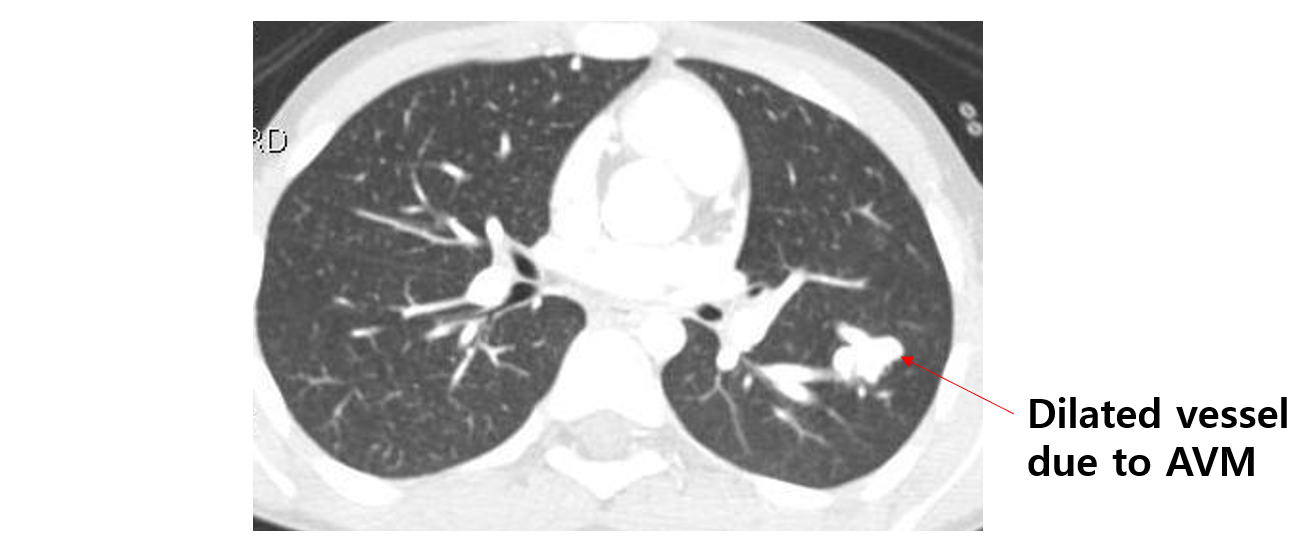

(1) 폐혈관 CT: Artery→vein shunt로 인해 dilated된 vessel 및 주변의 artery/vein